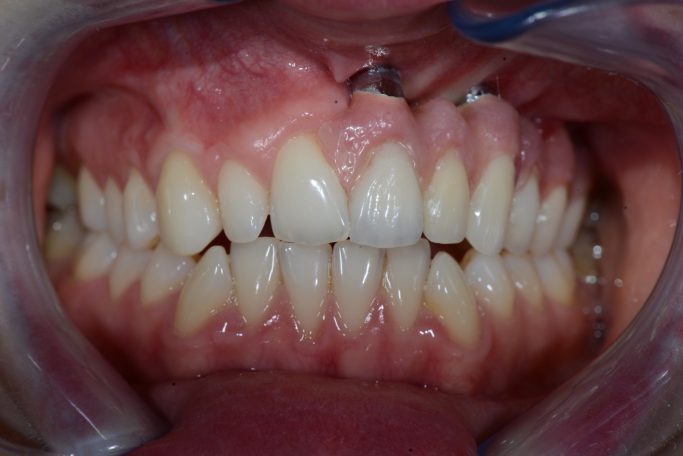

Teleskopierende Oberkieferbrücke mit Vorher- und Nachher-Situation des Patienten.

Teleskopierende Oberkieferbrücke. Wie die eigenen Zähne, aber einfach zu reinigen.